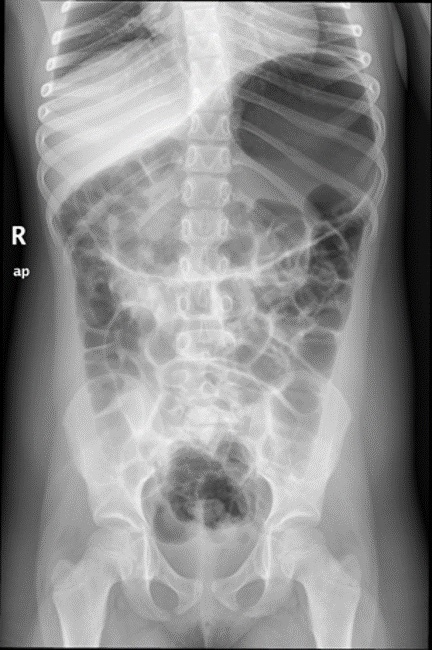

En la exploración física presenta un buen estado de nutrición, con un abdomen marcadamente distendido, timpánico, sin masas ni megalias, no doloroso a la palpación. Se realiza inicialmente radiografía simple de abdomen (Fig. 1), que muestra marcada distensión gástrica y abundante gas en todo el tracto gastrointestinal. Se realiza analítica con hemograma en el que únicamente destaca eosinofilia leve (700 eosinófilos/mm3); bioquímica con perfil hepatorrenal, amilasa y proteína C reactiva normales, hormonas tiroideas y anticuerpos antitransglutaminasa negativos. Estudio de heces con coprocultivo, virus enteropatógenos, toxina de C. difficile y parásitos negativos. Se realiza tránsito baritado (Fig. 2), que muestra marcada distensión gástrica y abundante gas intestinal, con poca motilidad gástrica y paso rápido de contraste a duodeno, sin datos de obstrucción ni vólvulo gástrico. Se completa con una ecografía abdominal sin hallazgos significativos. Tras la realización del tránsito presenta de nuevo importante distensión (Fig. 3), que precisa la recolocación de la sonda nasogástrica. Se produce mejoría clínica tras la descompresión. Se cita en consultas externas para completar el estudio. Se plantea en aquel momento la realización de endoscopia o manometría antroduodenal, para valoración de trastornos de motilidad y la realización de nuevos estudios de imagen como enterorresonancia magnética o incluso laparoscopia exploradora para descartar causa anatómica (vólvulo gástrico intermitente, etc.). El enigma se resuelve a los tres días del alta, tras la expulsión en el contexto de un vómito de un helminto no plano, de 30 cm de longitud, compatible con Ascaris lumbricoides (Fig. 4). Tras la expulsión del nemátodo y la administración de tratamiento con mebendazol oral, presenta buena evolución, manteniéndose asintomática hasta la actualidad.

| Figura 3. Radiografía simple de abdomen realizada unas horas tras el tránsito baritado que muestra una distensión gástrica muy marcada |

|---|

![]() |